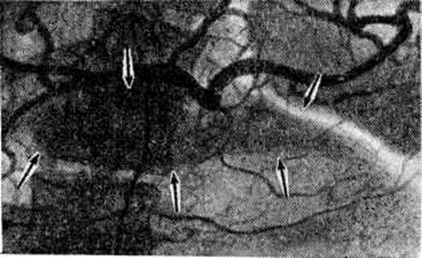

Охлаждение поджелудочной железы проводят путём локальной желудочной гипотермии (смотри полный свод знаний: Гипотермия искусственная, локальная) с помощью длительного промывания желудка холодной водой (открытый метод) или специальных охлаждающих аппаратов АГЖ-1 и другие (закрытый метод). Гипотермия позволяет в значительной мере подавить экскреторную функцию клеток железы. Однако длительность процедуры (4—6 часов), частое возникновение осложнений со стороны лёгких, выраженные нарушения кислотно-щелочного равновесия вследствие потерь желудочного сока при открытом методе ограничивают применение гипотермии в клинические, практике, особенно у больных пожилого и старческого возраста. С начала 70-х годы все более широкое применение для лечения острого Панкреатит находят различные цитостатики (5-фторурацил, циклофосфан, фторафур). Наиболее эффективно применение цитостатиков при регионарном введении в чревный ствол после катетеризации его по Сельдингеру — Эдману, что позволяет снизить дозу вводимого препарата, одновременно значительно повысив концентрацию его в тканях поджелудочной железы. По данным Джонсона (R. М. Johnson, 1972), А. А. Карелина и соавторами (1980), механизм лечебный действия цитостатиков при остром Панкреатит заключается в ингибировании экскреторной функции клеток поджелудочной железы. Экспериментальными исследованиями Ю. А. Нестеренко и сотрудники (1979) установлено, что внутриартериальное введение фторурацила в дозе 5 миллиграмм на 1 килограмм веса вызывает снижение внешне-панкреатической секреции на 91% и является оптимальной лечебный дозой. При внутривенном введении эта доза может быть увеличена в 2—3 раза. Применение цитостатиков показано при деструктивном Панкреатит Нецелесообразно их применение у больных с тотальным панкреонекрозом, гнойными осложнениями Панкреатит и почечно-печёночной недостаточностью. Выведение панкреатических ферментов и дезинтоксикация организма осуществляется с помощью методов внутривенного или внутриартериального введения диуретиков (для форсированного диуреза), перитонеального диализа и дренирования грудного лимфатических, протока. При форсированном диурезе панкреатические ферменты, компоненты кининовой системы, а также некоторые продукты клеточного распада выводятся почками. Методика форсированного диуреза включает водную нагрузку, введение диуретиков, коррекцию электролитного и белкового баланса. Основными компонентами вводимой жидкости могут быть 5—10% раствор глюкозы, раствор Рингера, реополиглюкин, солевой раствор. При внутривенном методе вводят ежесуточно 5—6 литров жидкости на протяжении 3—10 суток Форсирование диуреза осуществляют путём введения после инфузии каждых 2 литров жидкости мочегонных препаратов (лазикса, маннитола) и добиваются, чтобы суточный диурез достигал 3½—4 литров. По данным Г. А. Буромской и сотрудники (1980), внутриартериальное введение диуретиков более эффективно ликвидирует вне и внутриклеточную гидратацию, не повышает центральное венозное давление, не вызывает гиперволемию. В то же время при этом методе токсические продукты выводятся непосредственно из клеток поджелудочной железы, что обусловливает более выраженный дезинтоксикационный эффект. Объем вводимой внутриартериально жидкости зависит от интоксикации и степени дегидратации больного и составляет в среднем 4—5 литров в сутки. Продолжительность внутриартериального введения жидкости обычно составляет 3—4 суток При проведении форсированного диуреза необходим контроль за центральным венозным давлением, гематокритом, средним диаметром эритроцитов, показателями объёма циркулирующей крови, кислотно-щелочным равновесием, уровнем электролитов. Важную роль в борьбе с ферментативной токсемией играют антиферментные препараты (трасилол, контрикал, тзалол, пантрипин, гордокс и другие). Их необходимо вводить в больших дозах в течение 3—5 дней. Дренирование грудного лимфатических, протока (смотри полный свод знаний: Грудной проток) осуществляют при деструктивных формах панкреатита с целью выведения из организма ферментов поджелудочной железы. Количество удаляемой лимфы зависит от степени интоксикации и возможностей заместительной терапии. Лимфу, очищенную от токсических продуктов и панкреатических ферментов путём фильтрации через ионообменные колонки (смотри полный свод знаний: Лимфосорбция), реинфузируют в вену. По данным В. М. Буянова и сотрудники (1979), перспективным методом дезинтоксикации организма при остром Панкреатит является внутривенная жидкостная лимфостимуляция. Перитонеальный диализ (смотри полный свод знаний) показан при обнаружении в брюшной полости во время лапароскопии или лапаротомии большого количества серозного или геморрагического выпота. В зависимости от функции дренажей и состояния больного диализ продолжают 2—4 дня. Профилактику и лечение тромбоэмболических осложнений производят под контролем показателей тромбоз ластограммы и коагулограммы. При деструктивном Панкреатит уже в первые часы заболевания при наличии высокой фибринолитической активности и гипертрипсинемии для профилактики распространённого внутрисосудистого свёртывания крови целесообразно, кроме антиферментов, вводить также гепарин, низкомолекулярные растворы (5% раствор глюкозы, гемодез, реополиглюкин, поливинол, неокомпенсан и др.). Коррекцию электролитного обмена производят введением изотонического или 10% раствора хлорида натрия, 10% раствора хлорида калия, 1% раствора хлорида кальция, раствора Рингера — Локка и другие. При нарушении углеводного обмена вводят необходимые дозы глюкозы и инсулина. С целью коррекции белкового обмена переливают кровь, плазму, аминон, альбумин. Для профилактики гнойных осложнений, особенно в фазе расплавления и секвестрации некротических очагов в поджелудочной железе, применяют антибиотики широкого спектра действия (канамицин, гентамицин, мономицин, цепорин и другие). По данным В. С. Савельева (1977), наиболее эффективно введение антибиотиков в чрев-ный ствол. При некротических формах Панкреатит необходимо также стимулировать репаративные процессы в поджелудочной железе и других органах. Для этого назначают пентоксил, метилурацил, анаболические гормоны. Все операции при остром Панкреатит целесообразно разделять на три группы: 1) экстренные и срочные, выполняемые в первые часы и дни заболевания; 2) отсроченные, которые производят в фазе расплавления и секвестрации некротических очагов поджелудочной железы и забрюшинной клетчатки, через 10—14 дней и позднее от начала болезни; 3) плановые, выполняемые в период полного прекращения острого воспаления в поджелудочной железе, через 4—6 недель от начала приступа, после завершения обследования больного (эти операции предназначены для профилактики рецидива острого Панкреатит). Показания к экстренным и срочным операциям: разлитой ферментативный перитонит; острый Панкреатит, обусловленный холедохолитиазом (обтурацией большого сосочка двенадцатиперстной кишки). При экстренных и срочных операциях после лапаротомии через верхнесрединный разрез (смотри полный свод знаний: Лапаротомия) производят ревизию брюшной полости, выясняя состояние поджелудочной железы, забрюшинной клетчатки, париетальной брюшины и желчевыводящих путей. При отёчном Панкреатит в брюшной полости иногда обнаруживают серозный или желчный выпот. Поджелудочная железа увеличена в объёме, плотна на ощупь, на бледной или матовой поверхности её видны точечные кровоизлияния. При геморрагическом панкреонекрозе обнаруживаются кровянистый выпот, нередко с гнилостным запахом, часто с примесью желчи, при гнойном Панкреатит— мутный выпот с фибрином. Поджелудочная железа при ранней стадии геморрагического панкреонекроза увеличена, поверхность её покрыта множественными кровоизлияниями. При тотальном панкреонекрозе она бурого или чёрного цвета, на большом и малом сальнике, париетальной брюшине, брыжейке тонкой и толстой кишок и других органах часто видны очаги стеато-некроза. Выпот с примесью желчи, пропитывание ею печёночно-дуоденальной связки, увеличение размеров желчного пузыря, расширение общего желчного протока свидетельствуют о Панкреатит, осложнённом желчной гипертензией. При отёчном Панкреатит после удаления выпота брюшную полость обычно зашивают наглухо после обкалывания железы раствором новокаина с антибиотиками и антиферментными препаратами. При выраженной геморрагической или желчной имбибиции забрюшинной клетчатки производят широкое вскрытие забрюшинного пространства вокруг железы и в боковых каналах живота (около-ободочно-кишечных бороздах). Операцию заканчивают дренированием сальниковой сумки, иногда в сочетании с оментопанкреатопексией, или дренированием брюшинной полости с последующим перитонеальным диализом. При обширном геморрагическом панкреонекрозе А. А. Шалимов с сотрудники (1978), В. И. Филин с сотрудники (1979), Холлендер (L. F. Hollender, 1976) и другие производят резекцию поджелудочной железы, чаще всего левостороннюю. При остром Панкреатит, протекающем с желтухой, обусловленной холедохолитиазом, производят холедохотомию (смотри полный свод знаний), удаляют камни, заканчивая операцию наружным дренированием общего желчного протока (смотри полный свод знаний: Дренирование). При вклиненных камнях большого сосочка двенадцатиперстной кишки производят пластику большого сосочка двенадцатиперстной кишки — трансдуоденальную папиллосфинктеропластику (смотри полный свод знаний: Фатеров сосок). В фазе расплавления и секвестрации некротических очагов поджелудочной железы производят некрэктомию и секвестрэктомию. Некрэктомия возможна не ранее чем через 2 недель от начала заболевания, так как зона некроза железы чётко определяется не ранее 10-го дня с момента приступа острого Панкреатит Секвестрэктомия, то есть удаление отторгнувшихся некротизированных участков железы и забрюшинной клетчатки, возможна обычно не ранее 3—4-й недель от начала заболевания. Операция в фазе расплавления и секвестрации заключается в широком вскрытии сальниковой сумки через желудочно-ободочную связку, в ревизии железы и забрюшинной клетчатки, удалении некротизированных тканей, дренировании и тампонаде сальниковой сумки и забрюшинного пространства. После операции через дренажи осуществляют активную аспирацию гнойного отделяемого. Плановые операции направлены в основном на санацию желчного пузыря и протоков (холецистэктомия, холедохолитотомия, холедоходуоденостомия и другие) и лечение заболеваний других органов пищеварения, служащих причиной рецидива острого Панкреатит (язвенной болезни желудка, двенадцатиперстной кишки, дивертикулов двенадцатиперстной кишки, дуоденостаза и другие). В послеоперационном периоде продолжают комплексное консервативное лечение острого Панкреатит Тампоны из сальниковой сумки меняют на 7—8-й день, стараясь формировать широкий раневой канал, который периодически промывают антисептическими растворами (фурацилина, риванола, йодинола). В фазе секвестрации могут возникать аррозивные кровотечения. Иногда они могут быть обусловлены нарушениями свёртывающей системы крови. При профузных кровотечениях производят обшивание и перевязку сосудов в ране или на протяжении или их эмболизацию, тампонаду или резекцию поджелудочной железы. При фибринолитических кровотечениях показаны прямые гемотрансфузии (смотри полный свод знаний: Переливание крови) и введение ингибиторов фибринолиза — γ-аминокапроновой кислоты, антиферментов и другие Свищи поджелудочной железы возникают вследствие продолжающейся гнойной деструкции её или после операции по поводу панкреонекроза. В большинстве случаев при консервативном лечении, особенно при применении рентгенотерапии, свищи заживают в течение нескольких недель или месяцев. Если количество отделяемого из свища в течение 2—3 месяцев не уменьшается, показано оперативное лечение. Ложная киста поджелудочной железы также образуется вследствие локального некроза органа. При этом через разрушенные выводные протоки продолжается секреция панкреатического сока в очаг деструкции, который отграничивается вновь образуемой соединительной тканью, постепенно образующей стенку кисты. Псевдокиста поджелудочной железы может нагноиться, перфорировать или, сдавливая соседние органы, вызывать непроходимость кишечника, общего желчного протока. Методом выбора при оперативном лечении постнекротических псевдокист является панкреатоцистоэнтеро и панкреатоцистогастроанастомоз. При дистальном расположении кисты показана резекция поджелудочной железы; при нагноении кисты производят марсупиализацию (смотри полный свод знаний). ПрогнозПрогноз при остром Панкреатит всегда серьёзен. Общая летальность составляет от 3 до 7%, а летальность при панкреонекрозе — от 20 до 50%. В случаях панкреонекроза, потребовавших оперативного лечения, летальность колеблется от 30 до 85% . Отдалённые результаты лечения острого Панкреатит у 50% больных хорошие, более чем у 30% — удовлетворительные, у 15—20% развивается хронический Панкреатит. ПрофилактикаЦелесообразна диспансеризация больных, перенёсших острый Панкреатит Учитывая важную роль заболеваний желчных путей в возникновении острого Панкреатит, санация их является эффективной мерой профилактики рецидива заболевания. Необходимо также соблюдение диеты и исключение злоупотребления алкоголем. В период ремиссии рекомендуют санитарный-кур. лечение в санаториях желудочно-кишечные профиля (Боржоми, Железноводск, Трускавец, Краинка, Карлови Вари). Особенности острого панкреатита в пожилом и старческом возрастеПациенты пожилого и старческого возраста составляют более 25% больных острым Панкреатит Это объясняется прежде всего увеличением количества людей этого возраста среди населения. Немаловажное значение имеют также возрастные изменения в поджелудочной железе, в частности такие, как деформация протоков с облитерацией и расширением их, запустевание кровеносной капиллярной сети, фиброз междольковых перегородок и др. Способствуют более частому развитию острого Панкреатит и функциональный нарушения органов пищеварения, характерные для этого возраста, а также часто встречающиеся заболевания печёночных и желчных протоков, желудка, двенадцатиперстной и толстой кишок, сердечно-сосудистой системы. Наряду с обычной патоморфологические картиной заболевания у больных этой возрастной группы нередко наблюдается апоплексия поджелудочной железы или массивные жировые некрозы при липоматозе стромы железы. Клинические, проявления острого Панкреатит в этой группе больных характеризуются рядом особенностей. В связи с частым наличием у них разнообразных сопутствующих заболеваний даже лёгкие формы острого Панкреатит нередко протекают с выраженным нарушением функций жизненно важных органов и систем. Поэтому течение заболевания чаще сопровождается развитием острой сердечнососудистой, дыхательной, печёночно-почечной недостаточности, различных видов энцефалопатий и нарушением инкреторной функции поджелудочной железы. Это проявляется желтухой, олиго и анурией, гипо или гипергликемией. В то же время характерна незначительная болезненность при пальпации в надчревной области и выраженный парез желудочно-кишечные тракта. Комплексное консервативное лечение острого Панкреатит у больных пожилого и старческого возраста должно обязательно включать меры по лечению сопутствующих заболеваний, в первую очередь сердечно-сосудистой и дыхательной систем, профилактику и лечение печёночно-почечной недостаточности, нарушений углеводного обмена. В связи с этим лечение таких больных проводят в палате интенсивной терапии или реанимационном отделении. Особенности острого панкреатита у детейОстрый Панкреатит у детей встречается редко. Этиология заболевания весьма разнообразна (некоторые инфекционные болезни, аллергические состояния и др.). В большинстве случаев этиологического факторы остаются неясными; в связи с этим у детей внезапно возникающие острые Панкреатит принято называть идиопатическими. Заболевание часто начинается с общего недомогания ребёнка, отказа от пищи и подвижных игр. Развивающаяся затем клинические, картина в известной мере зависит от формы острого Панкреатит Острый отёк поджелудочной железы у детей (особенно младшей возрастной группы) протекает сравнительно легко, симптомы менее выражены, чем у взрослых, и часто расцениваются педиатрами как «интоксикация неясной этиологии». Проводимое симптоматическое лечение приводит к быстрому улучшению общего состояния. Только специальное обследование позволяет поставить правильный диагноз. У детей старшего возраста заболевание начинается с острых болей в животе, вначале разлитых, а затем локализующихся в надчревной области или носящих опоясывающий характер. Реже наблюдается постепенное нарастание болей. Одновременно появляются многократная рвота, обильное слюноотделение. Ребёнок принимает вынужденное положение, чаще на левом боку. Температура тела нормальная или субфебрильная, язык влажен, умеренно обложен белым налётом. Пульс удовлетворительного наполнения, ритмичен, учащён, АД нормальное или слегка понижено. При осмотре отмечается бледность кожных покровов. Живот правильной формы, не вздут, участвует в акте дыхания. Пальпация передней брюшной стенки безболезненна, живот мягкий. Такое несоответствие между жестокими болями в животе и отсутствием объективных данных, говорящих о наличии острого заболевания органов брюшной полости, характерно именно для отёчной формы острого Панкреатит В крови отмечается умеренный лейкоцитоз, без значительного изменения формулы. Наиболее информативным и ранним диагностическим признаком является повышение активности амилазы в крови. Несколько позже повышается содержание амилазы в моче. Как правило, наблюдается умеренная гипергликемия. Геморрагический и жировой некроз сопровождается выраженной симптоматикой и тяжёлым течением. У детей младшего возраста заболевание проявляется быстро нарастающим беспокойством. Ребёнок кричит и мечется от болей, принимает вынужденное положение. Постепенно двигательное беспокойство сменяется адинамией. Дети старшего возраста обычно указывают на локализацию болей в верхних отделах живота, их опоясывающий характер, иррадиацию в надключичную область, лопатку. Появляется многократная рвота, изнуряющая ребёнка. Общее состояние прогрессивно ухудшается. Кожные покровы бледны, с цианотичным оттенком. Развиваются эксикоз, тяжёлая интоксикация. Язык сухой, обложен. Пульс частый, иногда слабого наполнения, АД постепенно снижается. Температура тела обычно субфебрильная, в редких случаях повышается до 38-39°. При гнойном Панкреатит в начале заболевания ещё более выражено несоответствие между субъективными признаками острого живота и отсутствием или малой выраженностью объективных данных. Живот у ребёнка активно участвует в акте дыхания. Перкуссия и пальпация незначительно болезненны. Напряжение мышц передней брюшной стенки выражено слабо. Затем развивается парез кишечника, болезненность при пальпации усиливается, появляются симптомы раздражения брюшины. Температура тела повышается, характерен значительный лейкоцитоз. Наступает нарушение водно-электролитного баланса, повышается количество сахара в крови. Резко нарастает концентрация амилазы в крови и моче. Снижение её уровня является плохим прогностическим признаком. Иногда у детей младшего возраста тяжёлый геморрагический или жировой некроз проявляется клинические, картиной острого прогрессирующего асцита. Рентгенологические исследование у детей, как правило, мало информативно. У детей старшего возраста при обоснованном подозрении на панкреонекроз можно применить лапароскопию. Дифференциальный диагноз острого Панкреатит у детей проводят с острым аппендицитом, кишечной непроходимостью и перфорацией полых органов. Лечение острого Панкреатит у детей преимущественно консервативное. Всем детям после установления диагноза назначают комплекс лечебный мероприятий, направленных на борьбу с болевым синдромом, интоксикацией и вторичной инфекцией. Важной задачей является создание функциональный покоя поджелудочной железы, блокада её ферментообразующей функции, борьба с нарушениями водноэлектролитного баланса. Комплексное консервативное лечение у детей при остром Панкреатит, диагностированном в ранние сроки (1—2-е сутки), обычно приводит к выздоровлению. При чётких клинические, признаках гнойного Панкреатит или перитонита показано оперативное вмешательство. У детей дошкольного возраста сложность дифференциальной диагностики часто приводит к необходимости распознавать острый Панкреатит во время лапаротомии, производимой по поводу предполагаемого острого аппендицита или другого заболевания. Оперативное лечение проводят по тем же принципам, что и у взрослых. Все дети, переболевшие острым Панкреатит, нуждаются в длительном (до 2 лет) диспансерном наблюдении у хирурга и эндокринолога. Хронический панкреатитХронический Панкреатит встречается часто — по секционным данным, от 0,18 до 6% случаев. Однако в клинические, практике это заболевание, по-видимому, встречается ещё чаще, но не всегда диагностируется. Обычно хронический Панкреатит выявляется в среднем и пожилом возрасте, несколько чаще у женщин, чем у мужчин. Хронический Панкреатит у детей встречается редко. Различают первичный хронический Панкреатит, при котором воспалительный процесс с самого начала локализуется в поджелудочной железе, и так называемый вторичный, или сопутствующий, Панкреатит, постепенно развивающийся на фоне других заболеваний желудочно-кишечные тракта, например, язвенной болезни, гастрита, холецистита и другие. Этиология и патогенезЭтиология первичного хронический Панкреатит разнообразна. В хронический форму может перейти тяжёлый или затянувшийся острый Панкреатит Но чаще хронический Панкреатит возникает постепенно под воздействием таких факторов, как бессистемное нерегулярное питание, частое употребление острой и жирной пищи, хронический алкоголизм, особенно в сочетании с дефицитом в пище белков и витаминов. По данным Бенсона (J. A. Benson), в США хронический рецидивирующий Панкреатит в 75% случаев возникает у больных, страдающих хронический алкоголизмом. Пенетрация язвы желудка или двенадцатиперстной кишки в поджелудочную железу также может привести к развитию хронический воспалительного процесса в ней. Среди других этиологического факторов следует назвать хронический нарушения кровообращения и атеросклеротическое поражение сосудов поджелудочной железы, инфекционные болезни, экзогенные интоксикации. Иногда Панкреатит возникает после операций на желчных путях или желудке. Более редкой причиной является поражение поджелудочной железы при узелковом периартериите, тромбоцитопенической пурпуре, гемохроматозе, гиперлипемии. В ряде случаев, по данным некоторых исследователей, в 10—15% причина хронический Панкреатит остаётся неясной. Предрасполагающими факторами в возникновении хронический Панкреатит являются также препятствия для выделения панкреатического сока в двенадцатиперстную кишку, вызванные спазмом или стенозом ампулы сфинктера Одди, а также недостаточностью его, которая облегчает попадание дуоденального содержимого в проток поджелудочной железы. Одним из ведущих механизмов развития хронический воспалительного процесса в поджелудочной железе является задержка выделения и внутриорганная активация панкреатических ферментов, в первую очередь трипсина и липазы (фосфолипазы А), осуществляющих аутолиз паренхимы железы. Активация эластазы и некоторых других ферментов ведёт к поражению сосудов поджелудочной железы. Действие кининов на мельчайшие сосуды приводит к развитию отёка. Гидрофильный эффект продуктов распада в очагах некроза ткани поджелудочной железы также способствует отеку, а в последующем — образованию ложных кист. В развитии, особенно прогрессировании хронический воспалительного процесса, большое значение имеют процессы аутоагрессии. При хронический гастрите (смотри полный свод знаний) и дуодените (смотри полный свод знаний) нарушается выработка энтерохромаффинными клетками слизистой оболочки желудка и двенадцатиперстной кишки полипептидных гормонов, которые участвуют в регуляции секреции поджелудочной железы. При хронический Панкреатит инфекционные происхождения возбудитель может проникнуть в поджелудочную железу из двенадцатиперстной кишки (например, при дисбактериозе, энтеритах) или из желчных путей (при холецистите, холангите) через протоки поджелудочной железы восходящим путём, чему способствуют дискинезии желудочно-кишечные тракта, сопровождающиеся дуоденопанкреатическим и холедохопанкреатическим рефлюксом. Патологическая анатомияПатологоанатомически хронический Панкреатит подразделяют на хронический рецидивирующий Панкреатит и хронический склерозирующий Панкреатит Хронический рецидивирующий Панкреатит по существу является пролонгированным вариантом острого мелкоочагового панкреонекроза, поскольку всякий рецидив болезни сопровождается образованием свежих очагов некроза паренхимы поджелудочной железы и окружающей жировой клетчатки. Макроскопически в период обострения железа представляется несколько увеличенной в объёме и диффузно уплотнённой. Микроскопически в ней обнаруживаются свежие и организующиеся очаги некроза паренхимы и жировой клетчатки, чередующиеся с рубцовыми полями, очагами обызвествления, мелкими псевдокистами, лишёнными эпителиальной выстилки. Отмечается также значительная деформация и расширение просвета выводных протоков, содержащих уплотнённый секрет и нередко микролиты. В ряде случаев наблюдается диффузно-очаговое обызвествление интерстиция, и тогда говорят о хронический кальцифицирующем Панкреатит Воспалительная инфильтрация из лейкоцитов наблюдается лишь в очагах свежего некроза паренхимы. Она постепенно стихает по мере организации очагов деструкции, сменяясь диффузно-очаговыми инфильтратами из лимфоидных, плазматических клеток и гистиоцитов. Многие исследователи считают эти инфильтраты проявлением аутоиммунной реакции замедленного типа, возникающей в ответ на постоянное антигенное воздействие из очагов деструкции ацинусов. Хронический склерозирующий Панкреатит отличается диффузным уплотнением и уменьшением поджелудочной железы в размерах. Ткань железы приобретает каменистую плотность и макроскопически напоминает опухоль. Микроскопически обнаруживают диффузный фокальный и сегментарный склероз с прогрессирующим разрастанием соединительной ткани вокруг протоков, долек и внутри ацинусов. Причиной склероза является постоянная убыль паренхимы, протекающая по типу некроза или атрофии отдельных ацинусов и групп ацинусов. В далеко зашедших случаях на фоне диффузного фиброза с трудом обнаруживаются небольшие островки атрофичной паренхимы. Наряду с этим отмечается выраженная пролиферация эпителия протоков с образованием аденоматозных структур, которые иногда трудно дифференцировать с аденокарциномой. В просветах расширенных выводящих протоков постоянно встречаются сгущённый секрет, кристаллические отложения извести, микролиты. В окружности протоков обнаруживается большое количество гиперплазированных панкреатических островков (Лангерганса). Новообразования ацинусов не происходит, некроз паренхимы железы замещается рубцом. Как и при рецидивирующей форме Панкреатит, среди полей фиброзной ткани можно обнаружить лимфоплазмоцитарные инфильтраты, являющиеся отражением аутоиммунных процессов. При этом морфологически в поджелудочной железе преобладают не некротические, а дистрофически-атрофические изменения ацинусов с медленным их замещением соединительной тканью. При всех вариантах хронический Панкреатит наблюдаются одинаковые осложнения. Чаще всего встречается рубцовая стриктура протока поджелудочной железы, а также закупорка его камнем или аденоматозным полипом. При этом возможна обтурация общего желчного протока с развитием механической желтухи. Иногда наблюдается тромбоз селезёночной вены. Нередко на фоне хронический Панкреатит развивается сахарный диабет, хотя в отличие от ацинусов островки Лангерганса хорошо регенерируют, и среди рубцовой ткани их всегда можно обнаружить. Клиническая картинаКлиническая картина хронический Панкреатит весьма вариабельна, но в большинстве случаев включает следующие симптомы: боль в надчревной области и левом подреберье; диспептические явления; так называемый панкреатогенные поносы; похудание, гипопротеинемию, симптомы полигиповитаминоза; признаки сахарного диабета. Боль локализуется в надчревной области справа (при преимущественной локализации процесса в области головки поджелудочной железы); при вовлечении в воспалительный процесс её тела боль наблюдается в надчревной области; при поражении её хвоста — в левом подреберье. Нередко боль иррадиирует в спину (на уровне X—XII грудных позвонков) или имеет опоясывающий характер, усиливается в положении больного лёжа на спине и может ослабевать в положении сидя, особенно при небольшом наклоне вперёд. Боль может иррадиировать также в область сердца, имитируя стенокардию, в левую лопатку, левое плечо, а иногда в левую подвздошную область. Интенсивность и характер болей различны; они могут быть постоянными (давящими, ноющими), появляться через некоторое время после еды (как при язвенной болезни), особенно после приёма жирной или острой пищи, или быть приступообразными по типу панкреатической колики. Диспептические симптомы (панкреатическая диспепсия) встречаются часто, особенно при обострении заболевания или тяжёлом течении болезни. Многие больные отмечают также потерю аппетита, отвращение к жирной пище. В то же время при развитии сахарного диабета больные могут ощущать сильный голод и жажду. Часто наблюдаются повышенное слюноотделение, отрыжка, тошнота, рвота, метеоризм. Стул в лёгких случаях нормальный, в более тяжёлых наблюдается склонность к поносам или чередование запоров и поносов. Однако в типичных далеко зашедших случаях хронический Панкреатит (при наличии явных признаков внешнесекреторной недостаточности поджелудочной железы) более характерными являются панкреатические поносы с выделением обильного кашицеобразного зловонного с жирным блеском кала. Вследствие развития внешнесекреторной недостаточности поджелудочной железы и нарушения процессов переваривания и всасывания в кишечнике нарастает похудание. Ему способствует обычно наблюдавшаяся у больных потеря аппетита, а также присоединение сахарного диабета. При тяжёлых формах заболевания возможны депрессия, ипохондрия и другие психические нарушения. При алкогольном Панкреатит нарушения психики могут быть обусловлены длительным действием алкоголя на центральная нервная система Течение заболевания обычно имеет затяжной характер. Выделяют 5 форм заболевания: 1) рецидивирующая форма, характеризующаяся отчётливыми периодами ремиссии и обострений процесса; 2) болевая форма, протекающая с постоянными болями, доминирующими в клинической картине; 3) псевдоопухолевая форма; 4) латентная (безболевая) форма; 5) склерозирующая форма, для которой характерны рано возникающие и прогрессирующие признаки недостаточности функций поджелудочной железы. При последней форме иногда наблюдается механическая желтуха вследствие сдавления общего желчного протока склерозированной головкой поджелудочной железы. Т. Г. Ренева с сотрудники (1978) выделяет 3 формы течения хронический Панкреатит: лёгкую, среднетяжёлую и тяжёлую. Последняя протекает с упорными поносами, дистрофическими расстройствами, нарастающим истощением. ОсложненияОсложнения: кисты, кальцификаты поджелудочной железы, сахарный диабет, тромбоз селезёночной вены, стеноз протока поджелудочной железы. На фоне длительного хронический Панкреатит возможно развитие рака поджелудочной железы. ДиагнозФизикальное исследование. При пальпации живота у больных хронический Панкреатит обычно характерна болезненность в надчревной области и левом подреберье. Рядом исследователей описаны болевые точки и зоны, болезненность в которых особенно характерна. Так, при поражении головки поджелудочной железы боль может отмечаться при давлении в так называемый панкреатической точке Дежардена, располагающейся в области проекции на переднюю брюшную стенку дистального отдела протока поджелудочной железы (приблизительно на расстоянии 5—7 сантиметров от пупка по линии, соединяющей пупок с правой подмышечной впадиной), или в более широкой холедохо-панкреатической зоне Шоффара, располагающейся между указанной выше линией, передней срединной линией тела и перпендикуляром, опущенным на последнюю линию из точки Дежардена. Нередко отмечается болезненность точки в реберно-позвоночном углу (симптом Мейо-Робсона). Иногда отмечается зона кожной гиперестезии соответственно зоне иннервации 8 — 10-го грудного сегмента слева (симптом Кача) и некоторая атрофия подкожной клетчатки в области проекции поджелудочной железы на переднюю брюшную стенку, описанная А. А. Шелагуровым (1970). Пропальпировать увеличенную и уплотнённую поджелудочную железу при хронический Панкреатит удаётся очень редко. Некоторое диагностическое значение может иметь аускультация надчревной области при полном выдохе: иногда слышен систолический шум, который возникает вследствие сдавления брюшной части аорты увеличенной и уплотнённой поджелудочной железой. Лабораторные методы исследования нередко выявляют у больных хронический Панкреатит умеренную гипохромную анемию, ускорение РОЭ, нейтрофильный лейкоцитоз, диспротеинемию за счёт повышенного содержания глобулинов, повышение активности трансаминаз и альдолазы в сыворотке крови. При поражении островкового аппарата поджелудочной железы выявляется гипергликемия (смотри полный свод знаний) и гликозурия (смотри полный свод знаний), однако для выявления лёгких степеней нарушения углеводного обмена необходимо исследование сахарной кривой с двойной нагрузкой глюкозой (смотри полный свод знаний: Углеводы, методы определения). При нарушениях внешнесекреторной функции поджелудочной железы обычно выявляется более или менее выраженная гипопротеинемия; в более тяжёлых случаях — нарушение электролитного обмена, в частности гипонатриемия (смотри полный свод знаний). Определение в дуоденальном содержимом, а также в крови и моче содержания ферментов поджелудочной железы позволяет дать оценку функциональный состояния органа. В дуоденальном содержимом, полученном с помощью двухканального зонда (смотри полный свод знаний: Дуоденальное зондирование), до и после стимуляции поджелудочной железы секретином и панкреозимином определяют общее количество сока, его бикарбонатную щёлочность, содержание трипсина, липазы и амилазы; в крови — содержание амилазы, липазы, антитрипсина; в моче — амилазы. Одновременное проведение исследования содержания панкреатических ферментов в дуоденальном соке, крови, а также амилазурии позволяет значительно точнее отразить состояние внешнесекреторной функции поджелудочной железы у больных хронический Панкреатит, чем раздельное проведение этих исследований в разные дни. Гиперамилазурия, достигающая при хронический Панкреатит иногда цифр 2048— 4096 единиц (по Вольгемуту), выявляется чаще, чем гиперамилаземия, однако увеличение амилазы мочи (до 256—512 единиц) иногда наблюдается и при других заболеваниях органов брюшной полости. Содержание ферментов в крови и моче повышается в период обострения Панкреатит, а также при препятствиях к оттоку панкреатического сока (воспалительный отёк головки железы и сдавление протоков, рубцовый стеноз большого сосочка двенадцатиперстной кишки и другие). В дуоденальном содержимом концентрация ферментов и общий объем сока в начальном периоде болезни могут быть несколько увеличенными, однако при выраженном атрофически-склеротическом процессе в железе эти показатели снижаются. Копрологическое исследование (смотри полный свод знаний: Кал) выявляет повышенное содержание в кале непереваренной пищи (стеаторея, креаторея, амилорея, китаринорея). По мнению Осте да (W. J. Austad, 1979), стойкая стеаторея при хронический II. появляется тогда, когда внешняя секреция поджелудочной железы снижается не менее чем на 90%. Рентгенодиагностика. При рентгенологическое исследовании желудочно-кишечные тракта обнаруживают в случае увеличения поджелудочной железы смещение желудка кверху и кпереди, расширение дуоденальной петли и уплощение медиального контура нисходящей части двенадцатиперстной кишки (рисунок 1). С помощью релаксационной дуоденографии (смотри полный свод знаний: Дуоденография релаксационная) на этом контуре можно выявить короткие ригидные участки, ряд заострённых углублений в виде игл (спикул), вдавления по краям большого сосочка двенадцатиперстной кишки. На обзорных снимках поджелудочной железы определяют также камни или отложения солей кальция (рисунок 2), а на компьютерных томограммах обнаруживают расширенный и деформированный проток поджелудочной железы. При холеграфии (смотри полный свод знаний) иногда находят сужение дистального отдела общего желчного протока. Большое значение в диагностике хронический Панкреатит имеет эндоскопическая ретроградная холангиопанкреатография (смотри полный свод знаний: Панкреатохолангиография ретроградная). В начале заболевания протоки поджелудочной железы не изменены или отмечается деформация мелких выводных протоков поджелудочной железы. В дальнейшем эти протоки сужаются, часть их облитерирована, а в других — могут определяться мелкие кистоподобные расширения. Просвет протока поджелудочной железы становится неравномерным, на стенках его появляются неровности и в давления. В случае формирования абсцессов и псевдокист контрастное вещество из разрушенных протоков проникает в паренхиму железы и обрисовывает в ней полости, позволяя уточнить их положение и величину. В отличие от псевдокист в абсцессах могут при этом выявляться некротические массы. При целиакографии можно выделить две формы хронический Панкреатит Для первой формы типичны увеличение поджелудочной железы, её гиперваскуляризация и негомогенное контрастирование в паренхиматозной фазе (рисунок 3). Вторая форма более характерна для Панкреатит с выраженными фиброзными изменениями в поджелудочной железе. Она отличается смещением и сужением сосудов и обеднением сосудистого рисунка. Паренхиматозная фаза отсутствует или ослаблена. При всех формах Тилени Арнешьё(H. Tylen, В. Arnesjo, 1973) наблюдали стенозы крупных артерий вне поджелудочной железы — собственной печёночной, гастродуоденальной, селезёночной. Контуры суженных участков оставались ровными, в то время как при раке поджелудочной железы они имели «изъеденный» характер. Псевдокисты выглядят как округлые аваскулярные образования, смещающие прилежащие артериальные ветви. Во время операции и в послеоперационном периоде (если в протоках поджелудочной железы или полости кисты оставлен катетер для дренажа) для уточнения состояния протоков можно провести панкреатографию (смотри полный свод знаний). Если после операции по поводу кисты образовался наружный или внутренний свищ поджелудочной железы, целесообразно проведение фистулографии (смотри полный свод знаний), которая позволяет охарактеризовать свищевой ход и остаточную полость кисты (рисунок 4). Радиоизотопное сканирование поджелудочной железы с меченным селеном-75 метионином также имеет определённое диагностическое значение. Эхография позволяет выявить наличие, характер и протяжённость морфологический изменений в поджелудочной железе. Дифференциальный диагноз часто очень труден. Хронический Панкреатит необходимо дифференцировать прежде всего с опухолью поджелудочной железы (смотри полный свод знаний); при этом большое значение имеют методы инструментальной диагностики: целиакография, эндоскопическая ретроградная холангиопанкреатография, компьютерная томография, эхография и радиоизотопное сканирование поджелудочной железы. Дифференциальный диагноз проводят также с желчнокаменной болезнью (смотри полный свод знаний), язвенной болезнью желудка и двенадцатиперстной кишки, хронический энтеритом и другие.